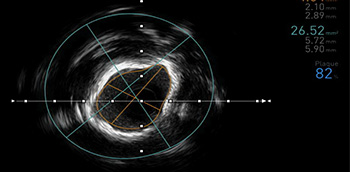

La técnica habitual para el diagnóstico de la enfermedad coronaria es la angiografía con contraste, y es en esta sobre la que está basada la mayor parte de la evidencia científica sobre el diagnóstico, pronóstico y manejo de esta patología. No obstante,...